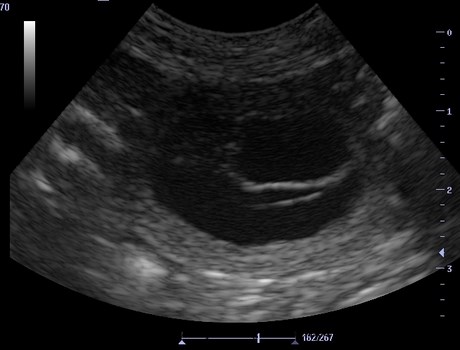

+++ Erste Bilder unserer Beaglebaby's - Ultraschall: +++

Bereits vor dem Ultraschall waren erste Anzeichen für die

Trächtigkeit zu erkennen:

Nadja 25. - 27. Trächtigkeits-Tag%20(Kopie).jpg)

+++ Halbzeit - Trächtigkeit +++

Die Hälfte der Tragzeit ist geschafft - Nadja genießt -

so schön kann "schwanger" sein !!! Nadja 30. - 33. Trächtigkeits-Tag:%20(Kopie).jpg)

31. Tag: Die Ausbildung der Organe ist abgeschlossen.

Die Föten sehen nun wie Hunde aus. Rumpf und Kopf sind unterscheidbar.

Fellfarbe entwickelt sich. Das Geschlecht ist zu bestimmen.

Der Herzschlag der Föten ist per Ultraschall sichtbar - per Stethoskop hörbar.![]()